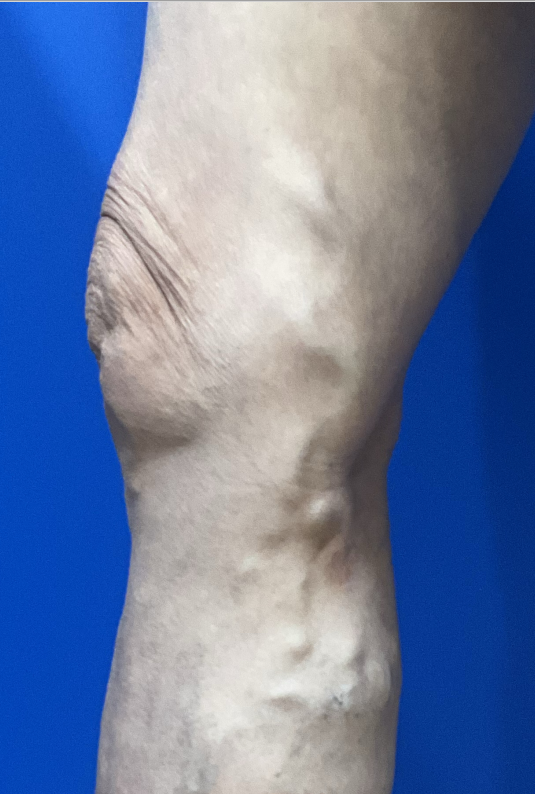

Before

1. 수술 전: 손가락 굵기만큼 돌출된 혈관

환자분은 허벅지부터 종아리까지

하지정맥류가 진행되어

손가락 크기만 한 혈관들이 울퉁불퉁하게

돌출되어 있는 것을 확인하실 수 있습니다.

단순히 보기 싫은 문제를 넘어,

정맥 역류로 인해 다리 무거움과 통증을

동반한 상태였습니다.